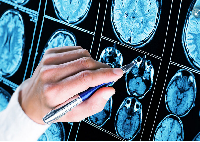

Магнитно-резонансная томография (МРТ):один из самых эффективных методов диагностики заболеваний